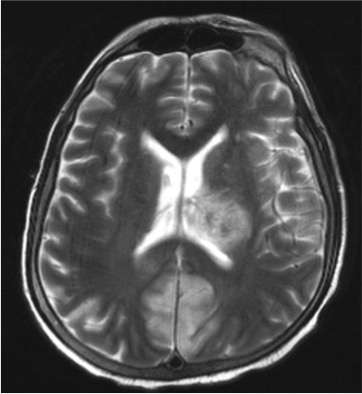

A middle-aged man presented with acute lymphoblastic leukemia (initial white cell count of 150,000 per cubic millimetre of blood – mostly blasts). After completing a course of hyper-CVAD, he developed persistent febrile neutropenia that was unresponsive to antibiotics. On the 6th day of fever, CT thorax was performed which was normal. On the 8th day of fever, he suddenly became drowsy and an MRI brain was performed. Sample images are shown below.

He was brought down to the intensive care unit (ICU) in view of his drowsiness and the brain lesions, and a skin lesion appeared over his face the following day.

These constellation of features suggest an opportunistic invasive fungal disease, and its rapidity of development is consistent with mucormycosis – a fungal infection caused by the Mucorales group of fungi. The following figure is a microscopic image of the fungus (Rhizopus spp.) cultured from this patient’s sinuses and skin lesion.